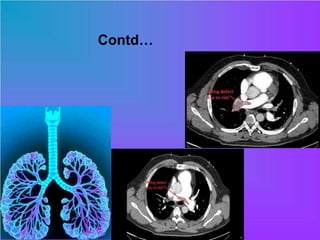

CT Pulmonary Angiography (CTPA)

• filling defects within the pulmonary

vasculature with acute pulmonary emboli

• When observed in the axial plane this has

been described as the polo mint sign

Contd… CT Pulmonary Angiography(CTPA) • filling defects within the pulmonary vasculature with acute pulmonary emboli • When observed in the axial plane this has been described as the polo mint sign